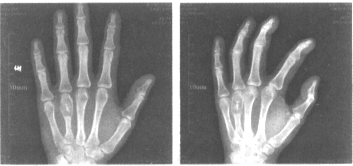

女,20岁,左手第4掌骨处局部稍肿痛,质硬,皮温不高。结合左手正斜位片,最可能的诊断为

• A.内生软骨瘤

• B.骨结核(骨气臌)

• C.骨囊肿

• D.骨巨细胞瘤

• E.非骨化性纤维瘤